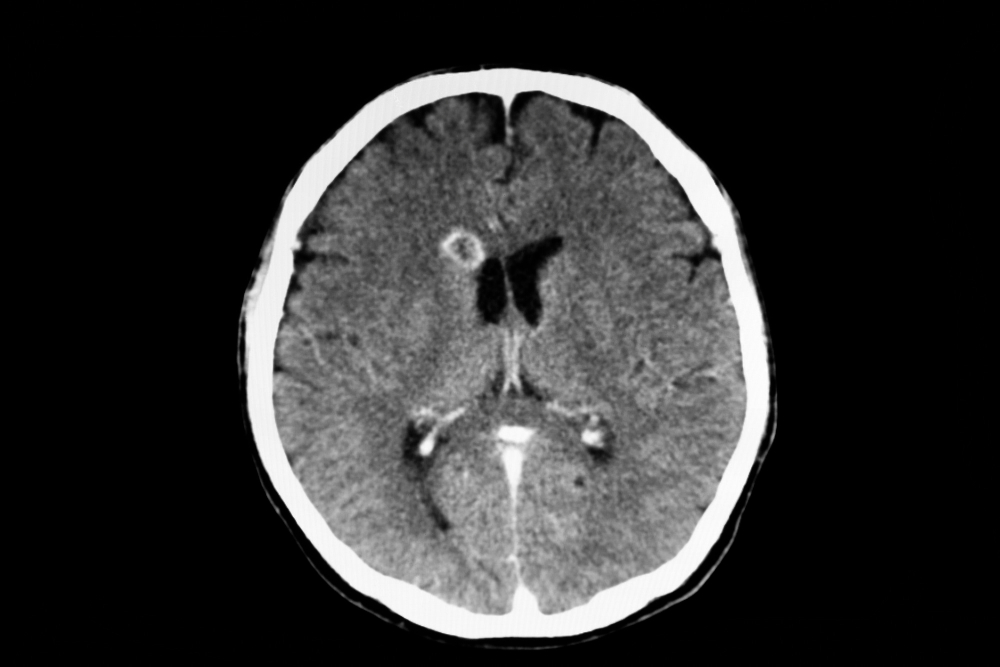

A craniotomy is a surgical procedure that involves temporarily removing a part of the skull to access and treat conditions affecting the brain, such as brain tumors, blood clots, or brain injuries.